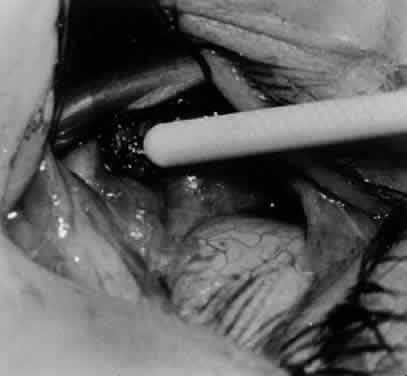

Fig. 24. The eyelid speculum is removed and a Desmarres lid retractor is placed inferiorly. The inferior oblique muscle is drawn superiorly and nasally. The fusiform expansion of the inferior oblique muscle is evident on the posterior border, where the nerve to the inferior oblique muscle and artery and vein enter the inferior oblique muscle. The Stevens muscle hook is used to hook the neurovascular bundle.

Fig. 25. The hook is advanced further for identification of the neurovascular bundle on the inferior oblique muscle.

Fig. 26. Cautery is applied to sever the neurovascular bundle, and a sponge is used to protect the sclera and lids from cautery.